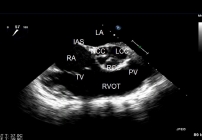

ECHO SERCA przezprzełykowe TEE

Echokardiograficzne badanie przezprzełykowe przeprowadza się w celu dokładniejszego zbadania serca.  Dzięki temu, że przełyk przylega bezpośrednio do serca uzyskiwane obrazy są bardzo szczegółowe.